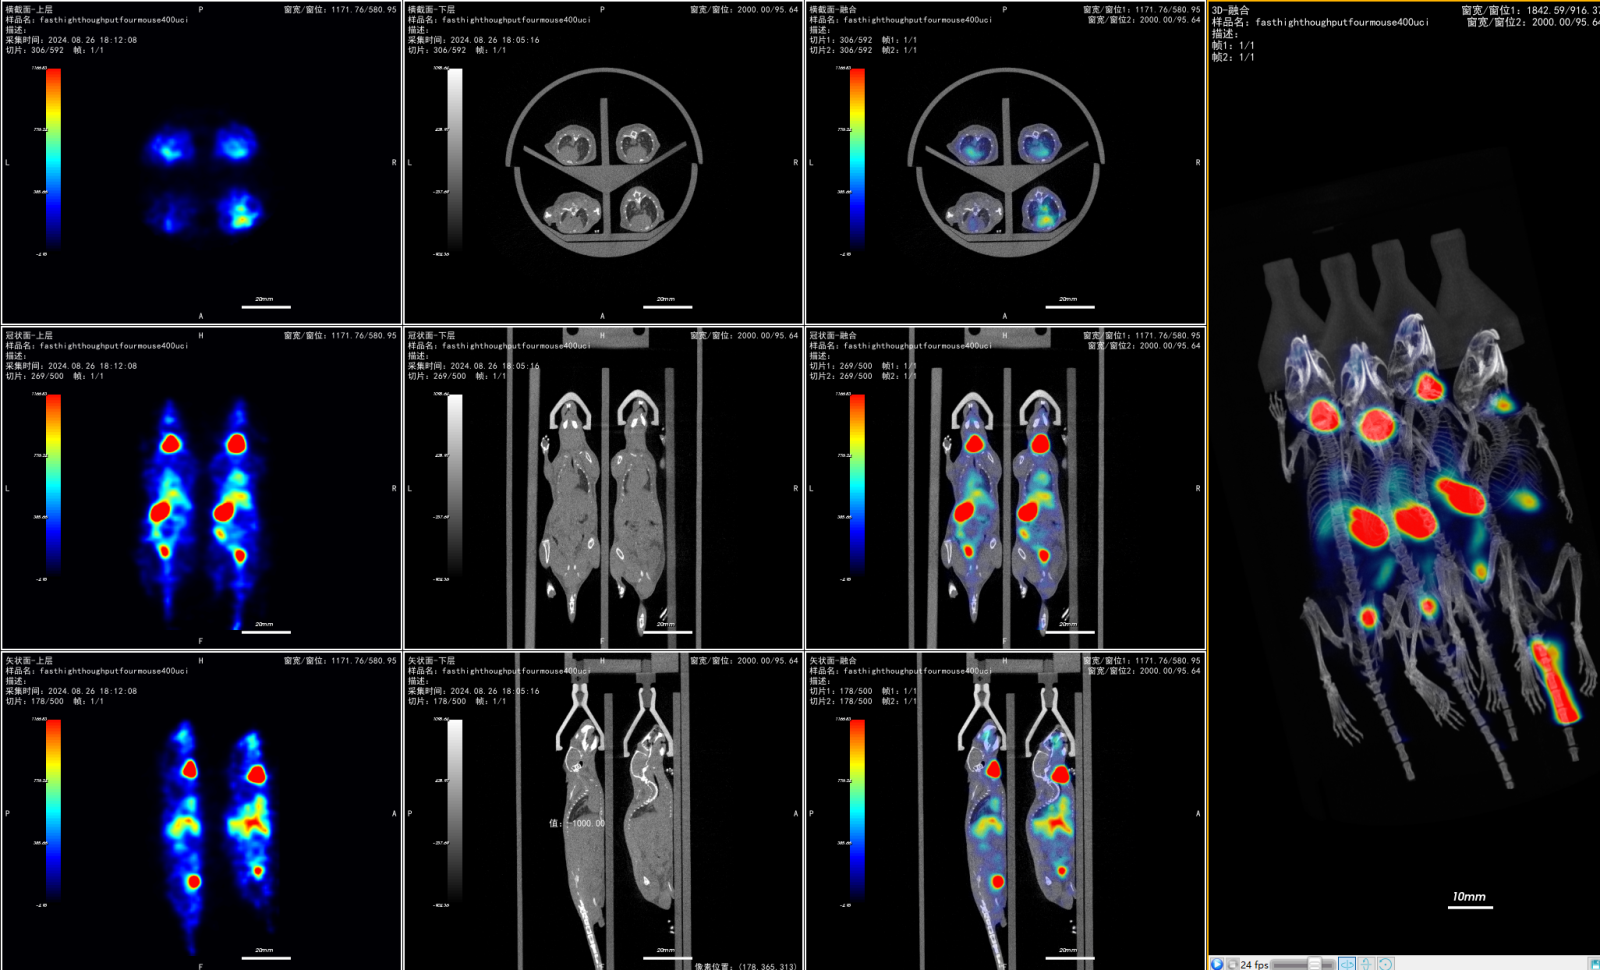

径向大视野及多通道的麻醉管路设计,支持4只小鼠的高通量扫描。

高通量特性结合创新的3D-PSF迭代重建技术(探测精度均衡),有助于提升药代动力学研究。

同步实现药物注射和数据采集。

实时跟踪示踪剂在动物体内的动态分布,

精确分析药物的代谢过程。